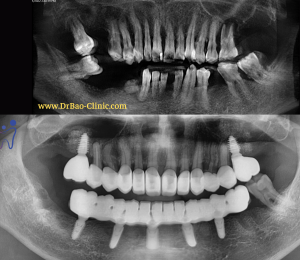

1/ Tình trạng ban đầu:

Đánh giá về chức năng:

- Khớp cắn rất sâu, gần như không thấy răng cửa dưới.

- Răng cửa dưới mòn nhiều

- Nhiều mão răng sứ bị hở tiếp xúc, viêm nhiễm do nhét thức ăn

- Răng 23,24 bị lung lay, có abcess quanh răng

4/ QUÁ TRÌNH ĐIỀU TRỊ GỒM 4 GIAI ĐOẠN:

- Giai đoạn 1: nhổ răng nhiễm trùng R23,24 + đặt 2 trụ implant có ghép xương và làm răng tạm tức thì

Giai đoạn 1: nhổ răng nhiễm trùng + đặt 2 trụ implant có ghép xương

Giai đoạn 4: phục hồi toàn miệng, bao gồm nâng khớp cắn